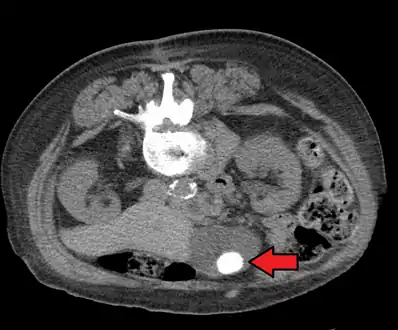

Diagnosis is typically confirmed by abdominal ultrasound. Other imaging techniques used are ERCP and MRCP. Gallstone complications may be detected on blood tests.[2]

Biliary sludge and gallstones. There is borderline thickening of the gallbladder wall.- Gallstones as seen on plain X-ray

Large gallstone as seen on CT- A normal gallbladder on ultrasound with bowel peristalsis creating the false appearance of stones